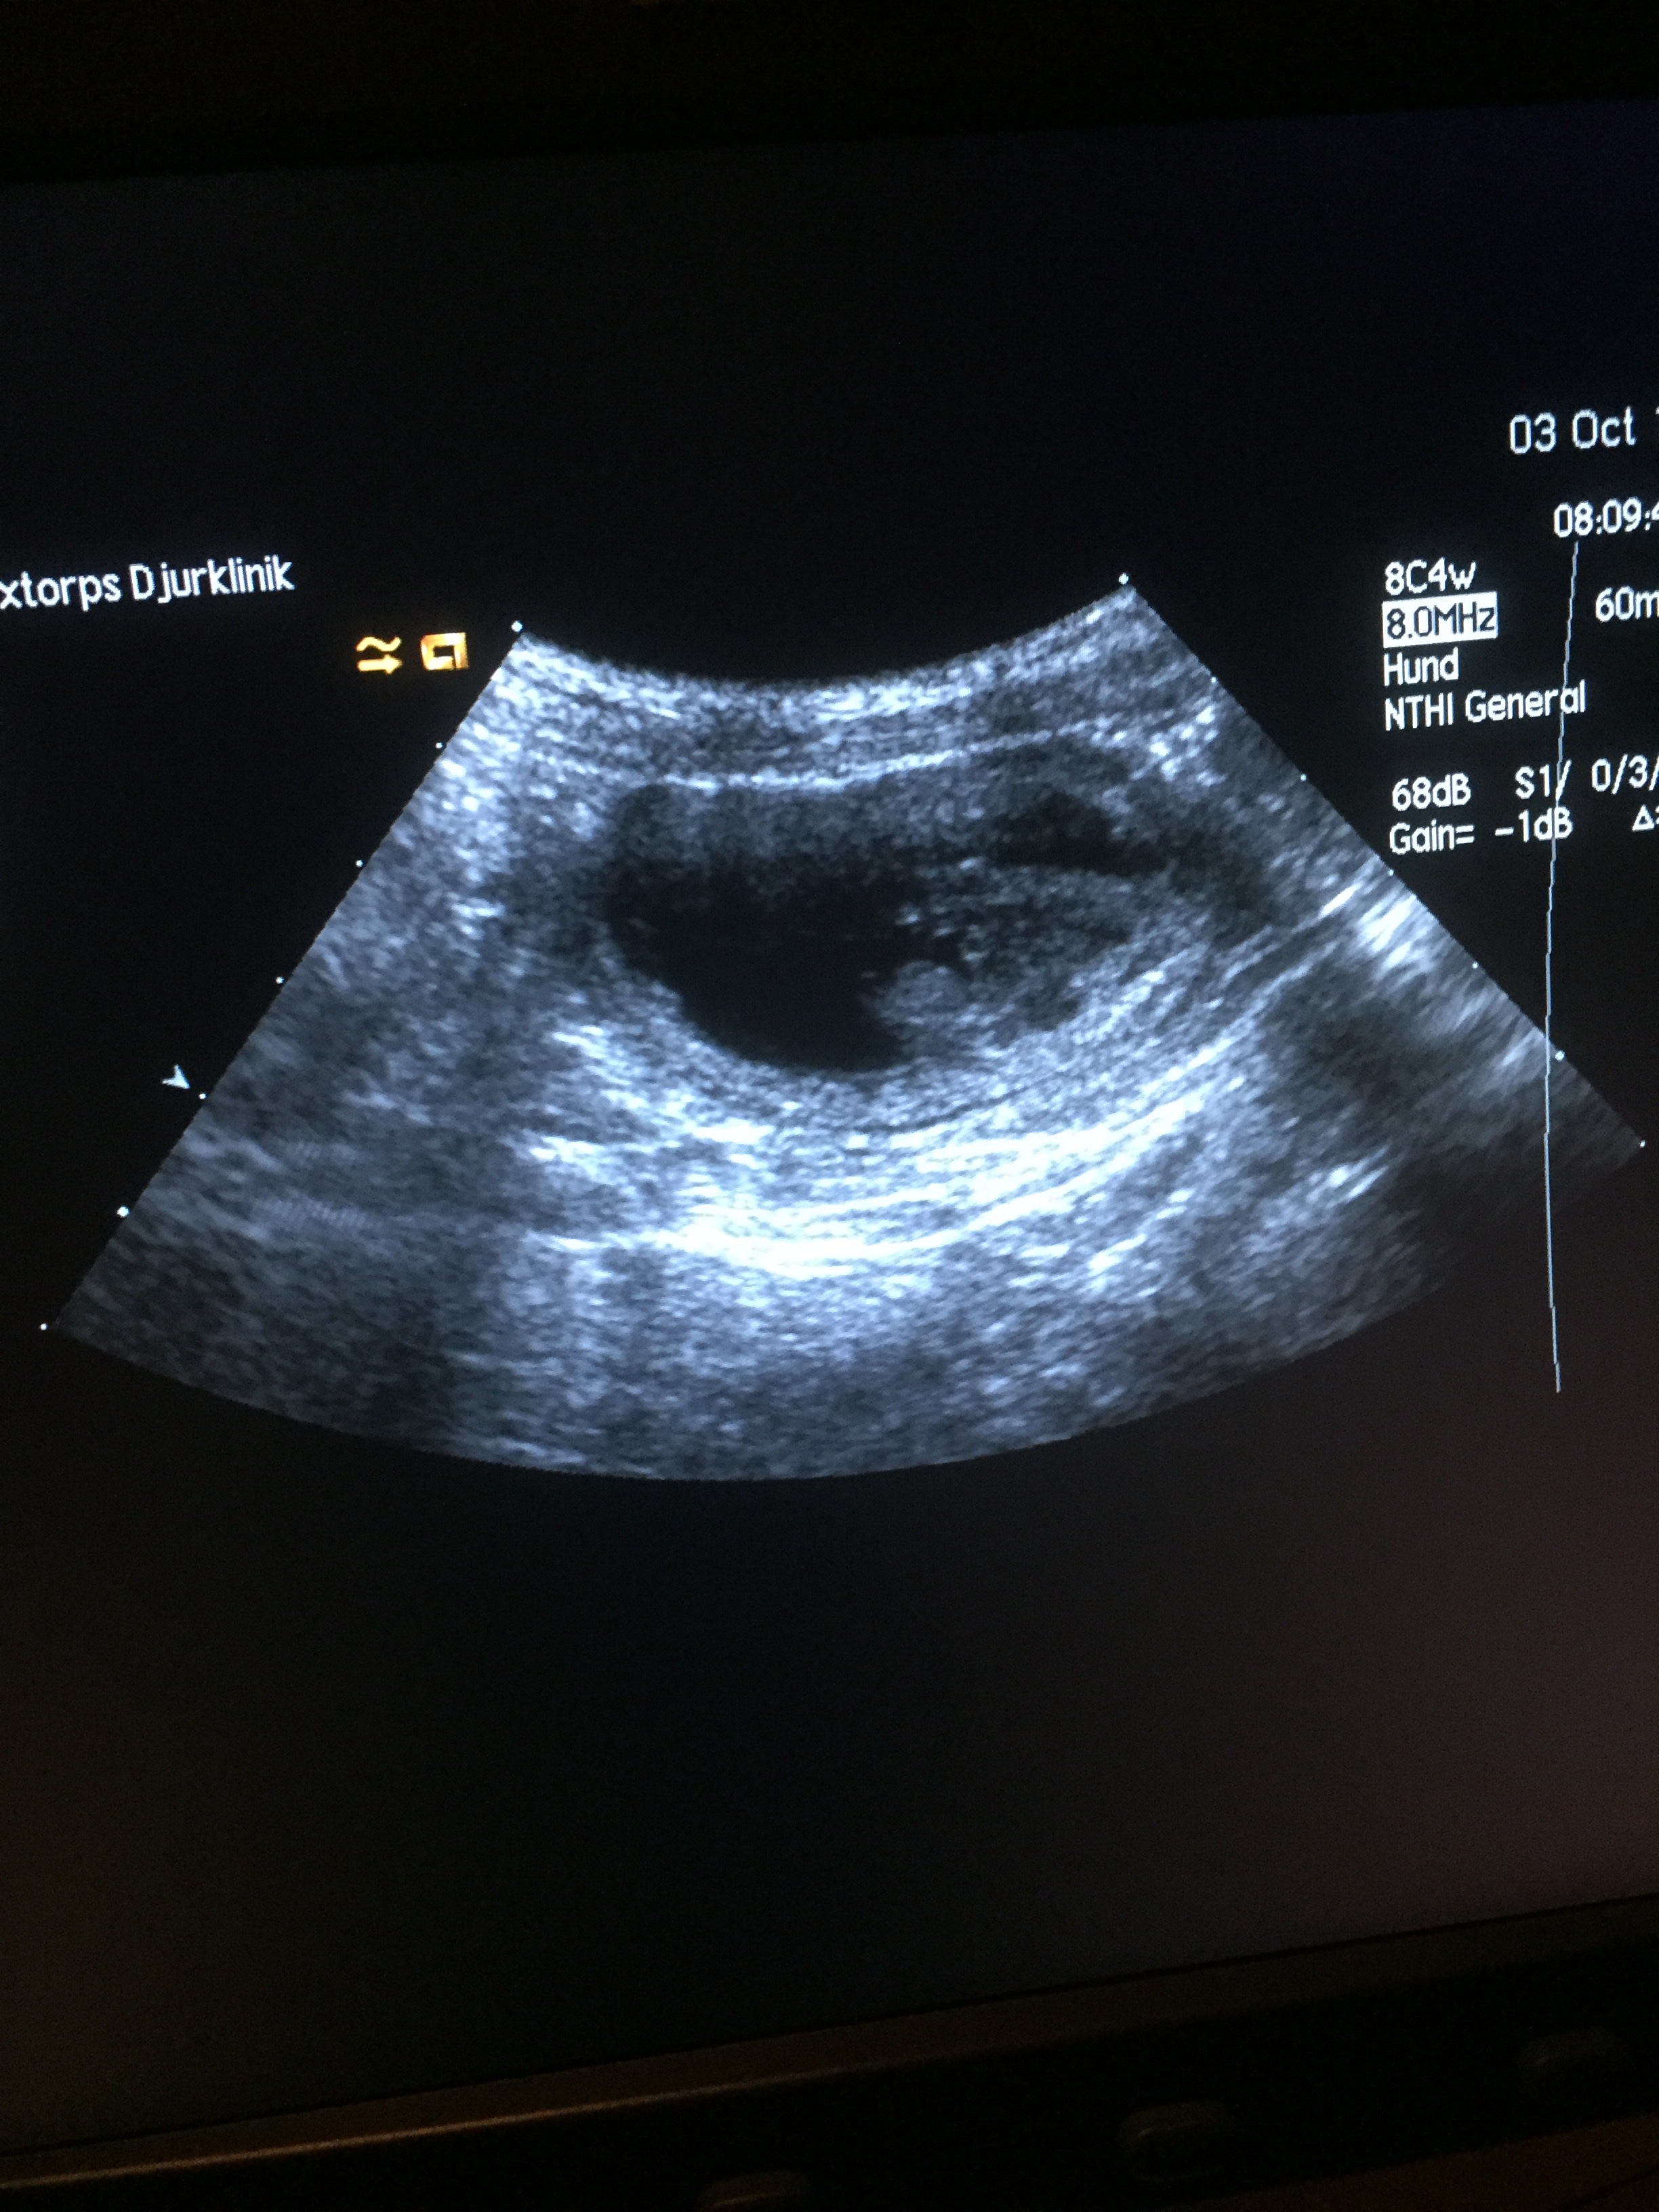

Idag fick vi den glada nyheten att Molly bär på Chesters valpar. Vilken lycka och glädje vi känner❤️. Det är dock mycket som kan hända under vägen men vi håller tummar och klor Molly för att allt ska gå bra. Det var så fantastiskt att se ena valpens pyttelilla hjärta slå💕. Molly beräknas föda sina valpar måndag V. 45 och då blir det ullgulliga valpar till jul🎅🏼🤶🏼🐾